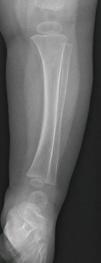

Niño de 12 meses, sin antecedentes de interés, que consulta por limitación para la deambulación de 24h de evolución, sin otra sintomatología acompañante. No historia de traumatismo ni cuadro catarral previo. En la exploración no se objetiva aumento de volumen articular, ni puntos dolorosos. Mantiene posición en reposo en flexo de cadera y rodillas, pero rechaza el apoyo de pie izquierdo en bipedestación. El resto de la exploración física es normal. Se realiza radiografía de tibia-peroné izquierda que muestra una fina línea de fractura en tibia distal solo en proyección lateral (figs. 1 y 2).

La fractura oculta, fractura de los primeros pasos o fractura de Toddler es una entidad propia de los niños menores de 3 años. Tras un traumatismo banal, el niño comienza con rechazo de la deambulación sin observarse, en la mayoría de los casos, otras alteraciones en la exploración física. En ocasiones, con una exploración minuciosa se puede apreciar un punto doloroso en la zona implicada. Radiológicamente es una fractura incompleta, no desplazada, de trayecto espiroideo muy fino, siendo el tercio distal de tibia, la región anatómica más frecuentemente afectada. Debido a sus características particulares, en ocasiones no se observa línea de fractura o solo es apreciada en una proyección radiológica1,2. Recientemente se ha propuesto la ecografía como método diagnóstico para confirmar la rotura cortical3.